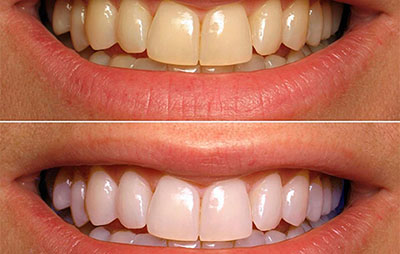

Можно ли отбеливать

Противопоказано при выраженных дефектах эмали, так как может спровоцировать проникновение болезнетворных микробов глубже.

Выходом из ситуации станут временные пломбы: их установят перед тем, как отбелить зубы, а постоянные будут подобраны уже под новообретённый цвет.

Выбор методов отбеливания — нанесение специального геля, ношение кап с осветляющим составом или отбеливающие полоски не играет принципиальной роли.